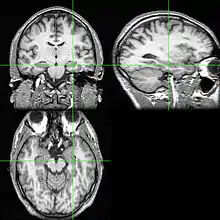

Os exames de neuroimagem podem identificar a causa das convulsões e o foco da convulsão, o local do cérebro onde as convulsões começam.[4] Na epilepsia recém-diagnosticada, a ressonância magnética (RM) pode detectar lesões cerebrais em até 12 a 14% das pessoas com epilepsia.[30] No entanto, para aqueles com epilepsia crônica, a RM pode detectar lesões cerebrais em 80% das pessoas com epilepsia.[30] A ressonância magnética 3-Tesla é recomendada para aqueles com evidência de epilepsia focal, como a epilepsia do lobo temporal.[4] As anormalidades identificadas pelo exame de RM incluem esclerose hipocampal, displasia cortical focal, outras malformações cerebrais de desenvolvimento cortical, tumores de desenvolvimento e de baixo grau, hemangioma cavernoso, lesão cerebral hipóxico-isquêmica, lesão cerebral traumática e encefalite.[4]